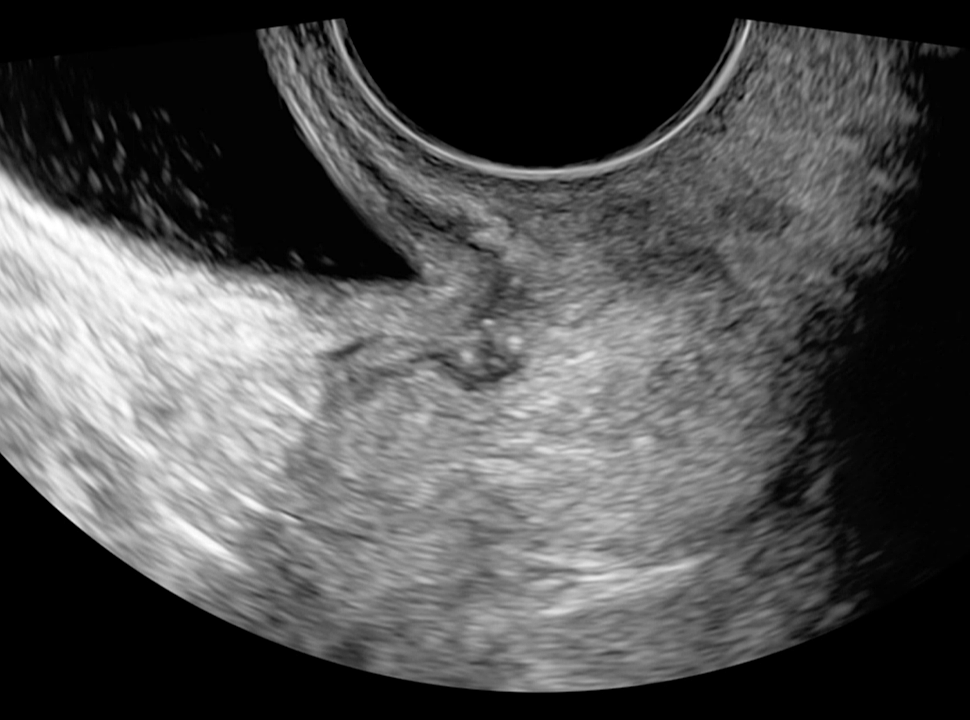

7

Ultrasound images of accessory cavitated uterine malformation (arrows), with uterine cavity denoted by star.25